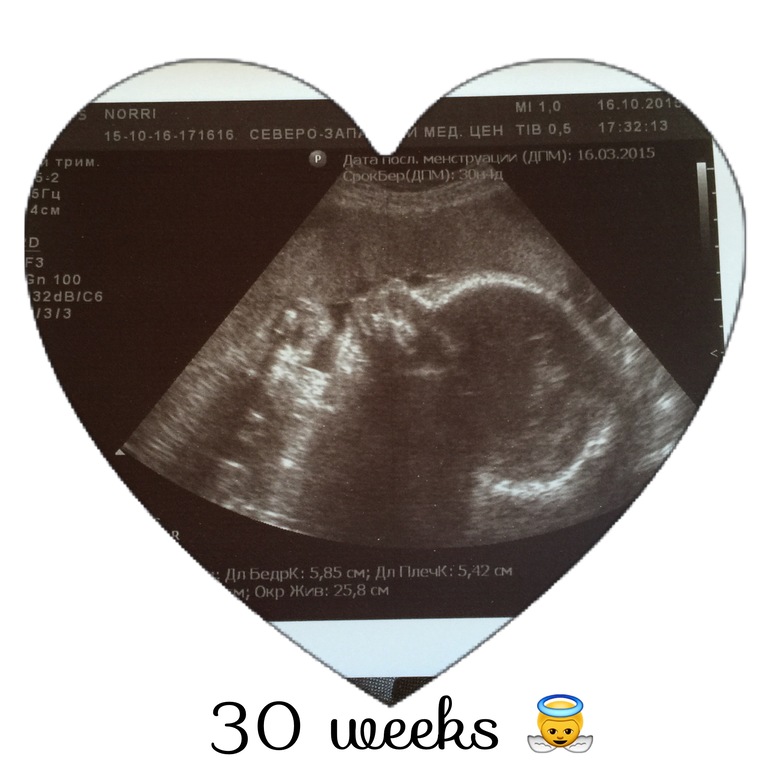

Узи в 30 недель

УЗИ, КТГ, доплерВчера съездила в Россию на узи. Женшина была приятная, все рассказала и показала, сделала фотографию. По прежнему у нас будет сыночек. Ох как я боялась что узист в 20 недель ошибся, но нет! Я рада! Наш сыночек весит 1553 грамма. И что удивительно лежит головкой вниз!😱 Два дня назад врач ощупывал и сказал что точно на попе сидит. И самое странное я не заметила что бы он перевернулся или как то шевеления изменились. По узи все хорошо, соответствуем сроку! Слава богу! Теперь можно со спокойной душой ждать родов. Осталось каких-то 9 недель, а может даже и меньше, ой кошмар😱😃

Вот результаты узи: